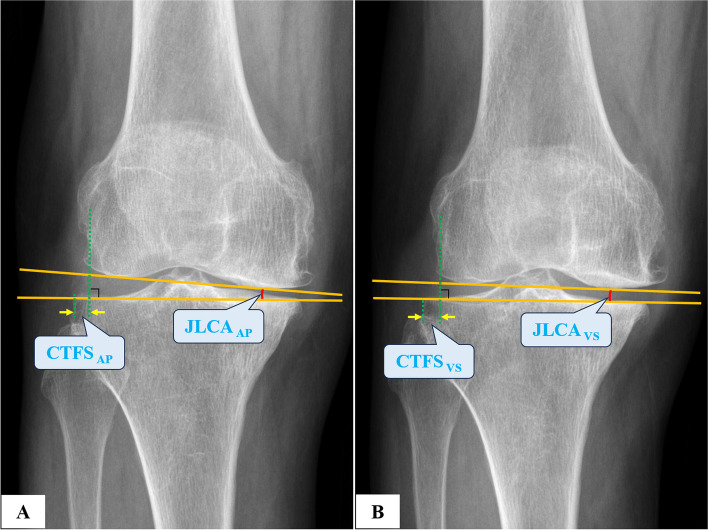

Methods: We analyzed 306 knees retrospectively using preoperative hip-to-ankle anteroposterior standing (APS) radiographs, anteroposterior (AP) and lateral knee radiographs, AP valgus stress (VS) force radiographs, and standard orthogonal MRI. Based on the intraoperative visualization, the knees were grouped into ACL functionally-intact and ACL functionally-deficient (ACLD) groups. The diagnostic validity and reliability were calculated based on the radiograph parameters such as hip-knee-ankle angle (HKA), medial proximal tibial angle (MPTA), lateral distal femoral angle (LDFA), posterior tibial slope (PTS), sagittal tibiofemoral subluxation (STFS), coronal tibiofemoral subluxation (CTFS), joint line convergence angle (JLCA), the maximum wear point of the proximal tibia plateau (MWPPT%), and MRI parameters including ACL grades and MWPPT%.